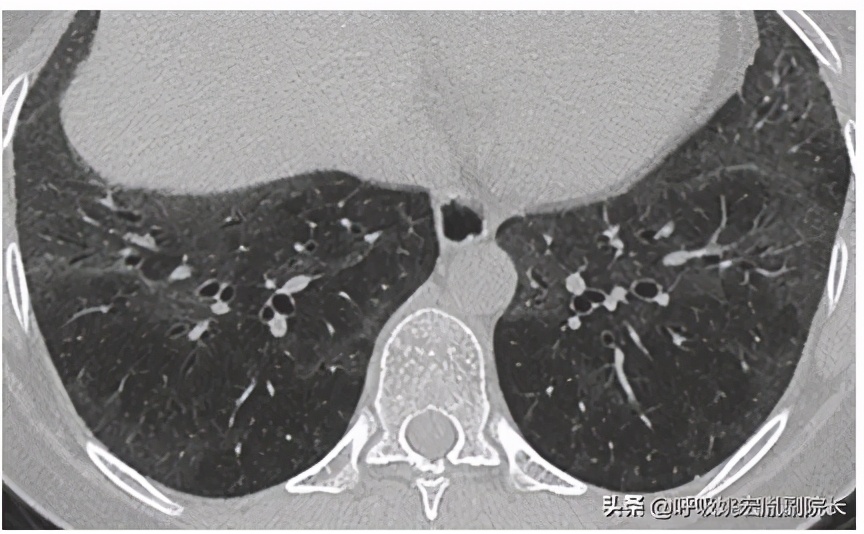

间质性肺炎是发生在肺间质的一种炎症,有的是由于病毒和支原体感染引起的,还有的是吸烟、尘肺等导致的,所以尘肺只是一种引起间质性肺炎的病因,而且得了尘肺后,治疗也是一个大问题,它没有什么好的治疗方法,只能通过改善症状来防止病情加重。

间质性肺炎是无法根治的。它是发现在肺间质的一种病理性改变,而且它的病因和病理也不是很明确,所以完全根治是不可能的,只能通过检查来对症处理,然后进行治疗改善它的症状,还有一种就是根据它的病因来做针对治疗,可以相对的减轻症状,防止间质性肺炎进一步恶化。